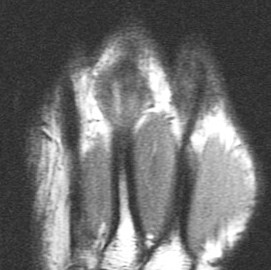

Figure 3 for case Boxers knuckle

Figure 3